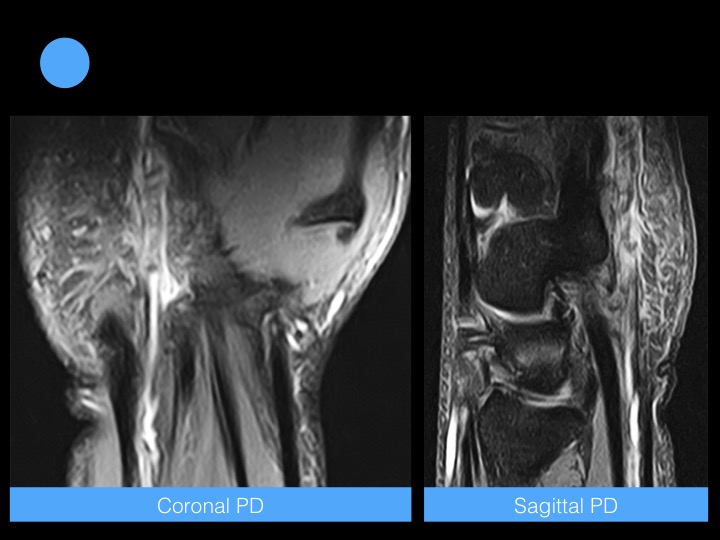

45-year-old man with unspecific pain and numbness in the hypothenar eminence

Hypothenar hammer syndrome is caused by blunt repetitive injury to the ulnar artery and superficial palmar arch from impact against the hamulus. Palmar arches and digital arteries also may be occluded.

Intimal hyperplasia is almost invariably present. Arterial wall damage may lead to aneurysm formation with or without vessel thrombosis and to microemboli formation and compression of the sensory branch of the ulnar nerve.

The diagnosis can be confirmed easily with Doppler ultrasound. However, CT angiography, or MR angiography is for precise vascular mapping. Reference article.

Hypothenar Hammer Syndrome